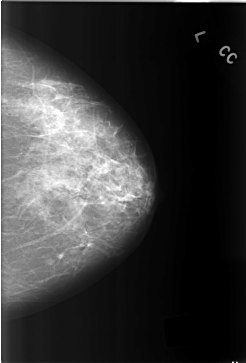

C_0304_1.LEFT_CC

LEFT_CC LINES 5800 PIXELS_PER_LINE 3928 BITS_PER_PIXEL 12 RESOLUTION 50 NON_OVERLAY